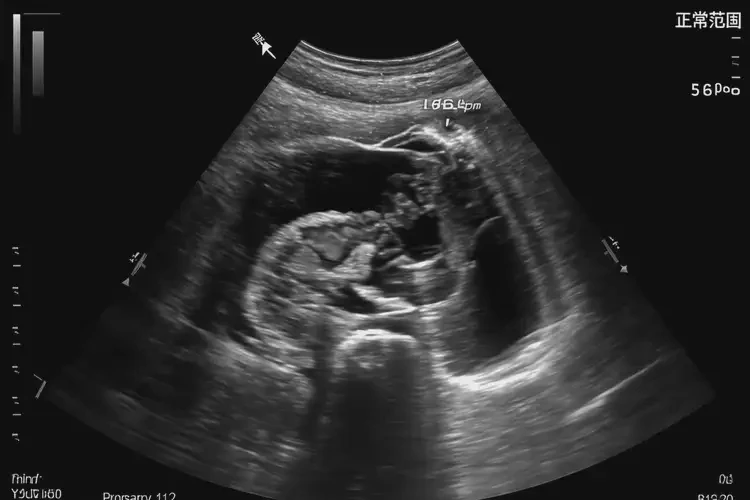

懷孕第5周胎心96有危險(xiǎn)嗎(圖1)

懷孕第5周胎心96有危險(xiǎn)嗎(圖2)

懷孕第5周胎心96有危險(xiǎn)嗎(圖3)

懷孕第5周胎心96有危險(xiǎn)嗎(圖4)